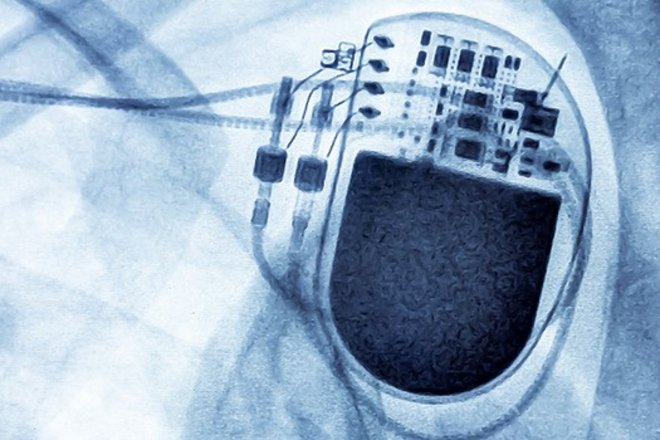

wir freuen uns sehr, Sie zu unserer Fachveranstaltung „Workshop Advanced Programming – Interaktives Seminar zur Schrittmacherprogrammierung“ am 11. März 2026 im Marien Hospital Herne einladen zu dürfen. Die Schrittmachertherapie hat in den letzten Jahren unter anderem durch die Entwicklung kabelloser Schrittmachergeräte zur Reduktion sondenassozierter Komplikationen wichtige Fortschritte erzielt. Zudem nehmen die biventrikuläre und die Stimulation des spezifischen Reizleitungssystems (CSP = conduction system pacing) zur Prävention und Therapie der Schrittmacherinduzierten Kardiomyopathie einen immer größeren Stellenwert ein.

Allerdings sind im Rahmen der Nachsorge von kabellosen Geräten als auch von CRT- und CSP-Geräten einige relevante Punkte zu beachten, um eine optimale Gerätefunktion sicherzustellen. Auf diese Aspekte wird in unserem interaktiven Seminar ausführlich eingegangen. Wir würden uns sehr freuen, Sie persönlich in Herne begrüßen zu dürfen und gemeinsam mit Ihnen in den kollegialen Austausch zu treten.